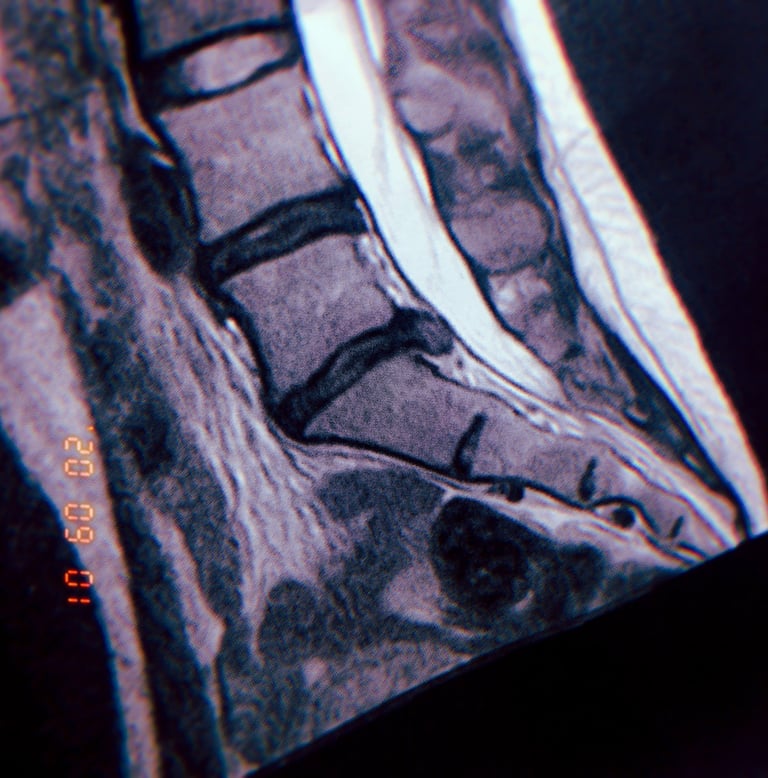

< MRI scan showing a herniated disc, a common ailment affecting individuals in the riding industry.

Grasping the fundamentals of seat awareness and biomechanics is crucial for preventing a range of health issues, including herniated discs. A herniated disc can lead to debilitating pain, stiffness, and in severe cases, nerve damage that results in a loss of sensation. This not only affects physical well-being but can also significantly diminish one’s overall quality of life.

By learning about proper seating posture and the mechanics of your seat, you can avoid common pitfalls that contribute to these serious conditions. Investing time in understanding how your seat can impact your health is essential for maintaining comfort and preventing long-term complications.